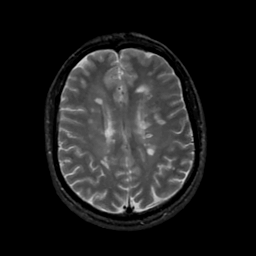

MR Study #17, July 7, 1991 -- Slice #33